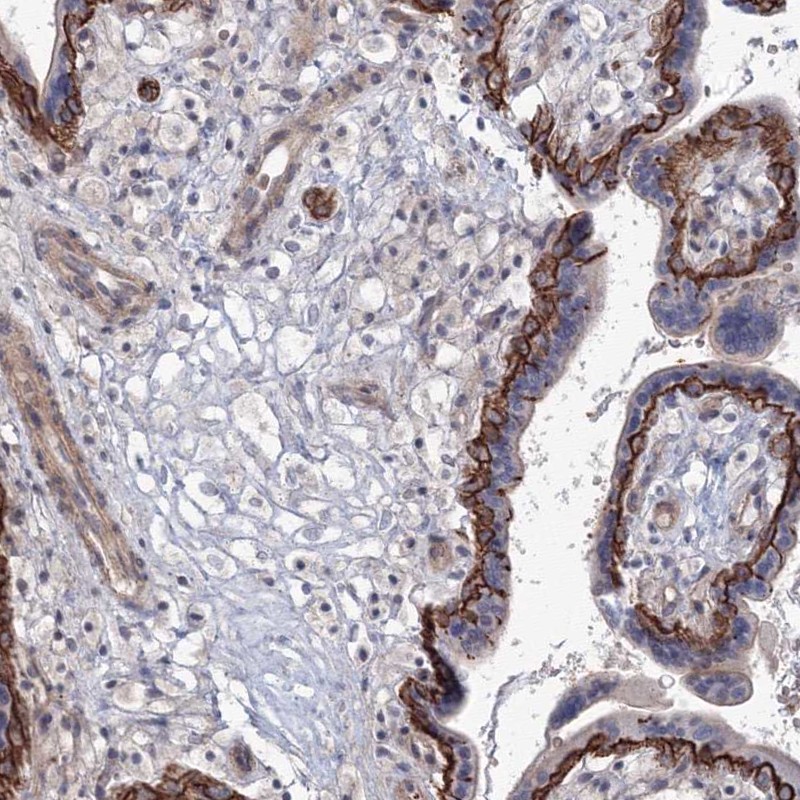

Immunohistochemical staining of human placenta shows strong membranous positivity in trophoblastic cells.